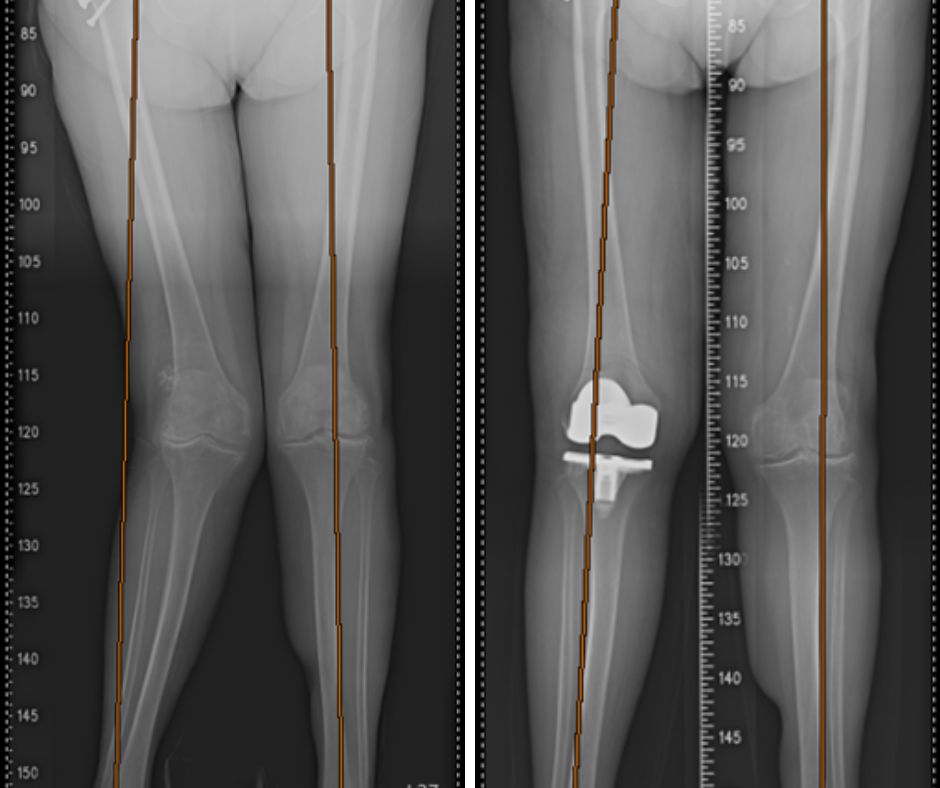

84歲陳女士,多年來受右膝嚴重外翻影響,外觀呈X型腿,走路時兩側膝蓋常互相碰撞,導致步態不穩。一年前她更因此跌倒,造成右側髖關節股骨頸骨折。經長安醫院骨科微創骨折手術與骨質疏鬆藥物治療滿一年後,她終於下定決心接受人工膝關節置換手術,術後兩週便能放下助行器行走,徹底擺脫多年的行走惡夢。

喻大久醫師說明,陳女士的膝蓋外翻案例,與多數退化性關節炎常見的內翻(O型腿)不同。外翻變形會導致膝蓋外側韌帶緊繃、內側韌帶鬆弛,並常伴隨股骨外側髁變形,因此手術手法與一般內翻型全膝關節置換有所差異。

喻醫師進一步解釋,手術核心在於韌帶平衡與角度矯正。術中必須對外側緊繃的韌帶進行適度放鬆,同時小心保護內側韌帶,以確保關節穩定。更重要的是,在置換人工關節時,需特別注意做出適當的外旋角度,才能確保髕骨在膝蓋彎曲、伸直時滑動平順,這是決定術後膝蓋功能是否好用的關鍵細節,並降低術後卡卡或不適的機率。

患者X型腿置入人工關節後,膝蓋活動起來非常平順,不再互相碰撞。